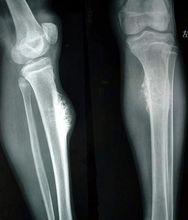

惡性骨腫瘤累及骨膜及骨外軟組織,刺激骨膜成骨,腫瘤繼而破壞骨膜所形成的骨質,其邊緣殘存骨質呈三角型高密度病灶,稱骨膜三角。是惡性骨腫瘤的重要徵象。長骨骨肉瘤位於乾骺端的骨髓腔中央或為偏心性。一側或四周的骨皮質被浸潤和破壞,其表面的骨外膜被掀起,切面上可見腫瘤上、下兩端的骨皮質和掀起的骨外膜之間形成三角形隆起,其間堆積由骨外膜產生的新生骨。此三角稱為 Codman三角,又稱骨膜三角。

日光放射狀陰影

是指在Codman三角形成時骨膜返向皮質的血管受到牽拉而垂直於骨皮質的分布,在垂直小血管周圍 由於血運豐富而致形成新生骨較多。於是出現這些反應性骨小梁呈放射狀與骨表面垂直分布。在X線片上即表現為日光放射狀陰影。

在骨肉瘤的典型X線片上可以出現Codman氏三角和日光放射狀陰影的表現,這是診斷骨肉瘤的特徵性表現。